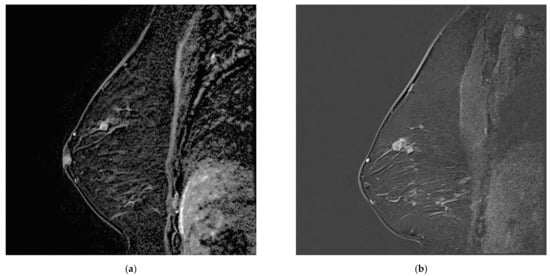

Breast lesions were first classified according to whether or not they were missed. The missed lesions were defined as visible on MR A (as a mass, non-mass enhancement, or focus standing out from background parenchymal enhancement) (Figure 1). The so-called missed lesions were subdivided into two categories, namely either overlooked, i.e., not described in the initial radiology report of MR A, or misinterpreted, either expressed as BI-RADS 2 or BI-RADS 3 on MR A, subsequently becoming BI-RADS 4 or BI-RADS 5 on MR B (Figure 1 and Figure 2). Non-missed lesions were defined as the absence of mass or non-mass enhancement on MR A. For each lesion, the MRI characteristics were documented according to the BI-RADS lexicon (T2 signal, size/volume, margins, distribution, enhancement and kinetics).

Figure 1. Examples of missed lesions. Overlooked linear non-mass enhancement: (a) MR A; (b) follow-up MRI (MR B) one year later showing more conspicuous non-mass enhancement, corresponding to DCIS.